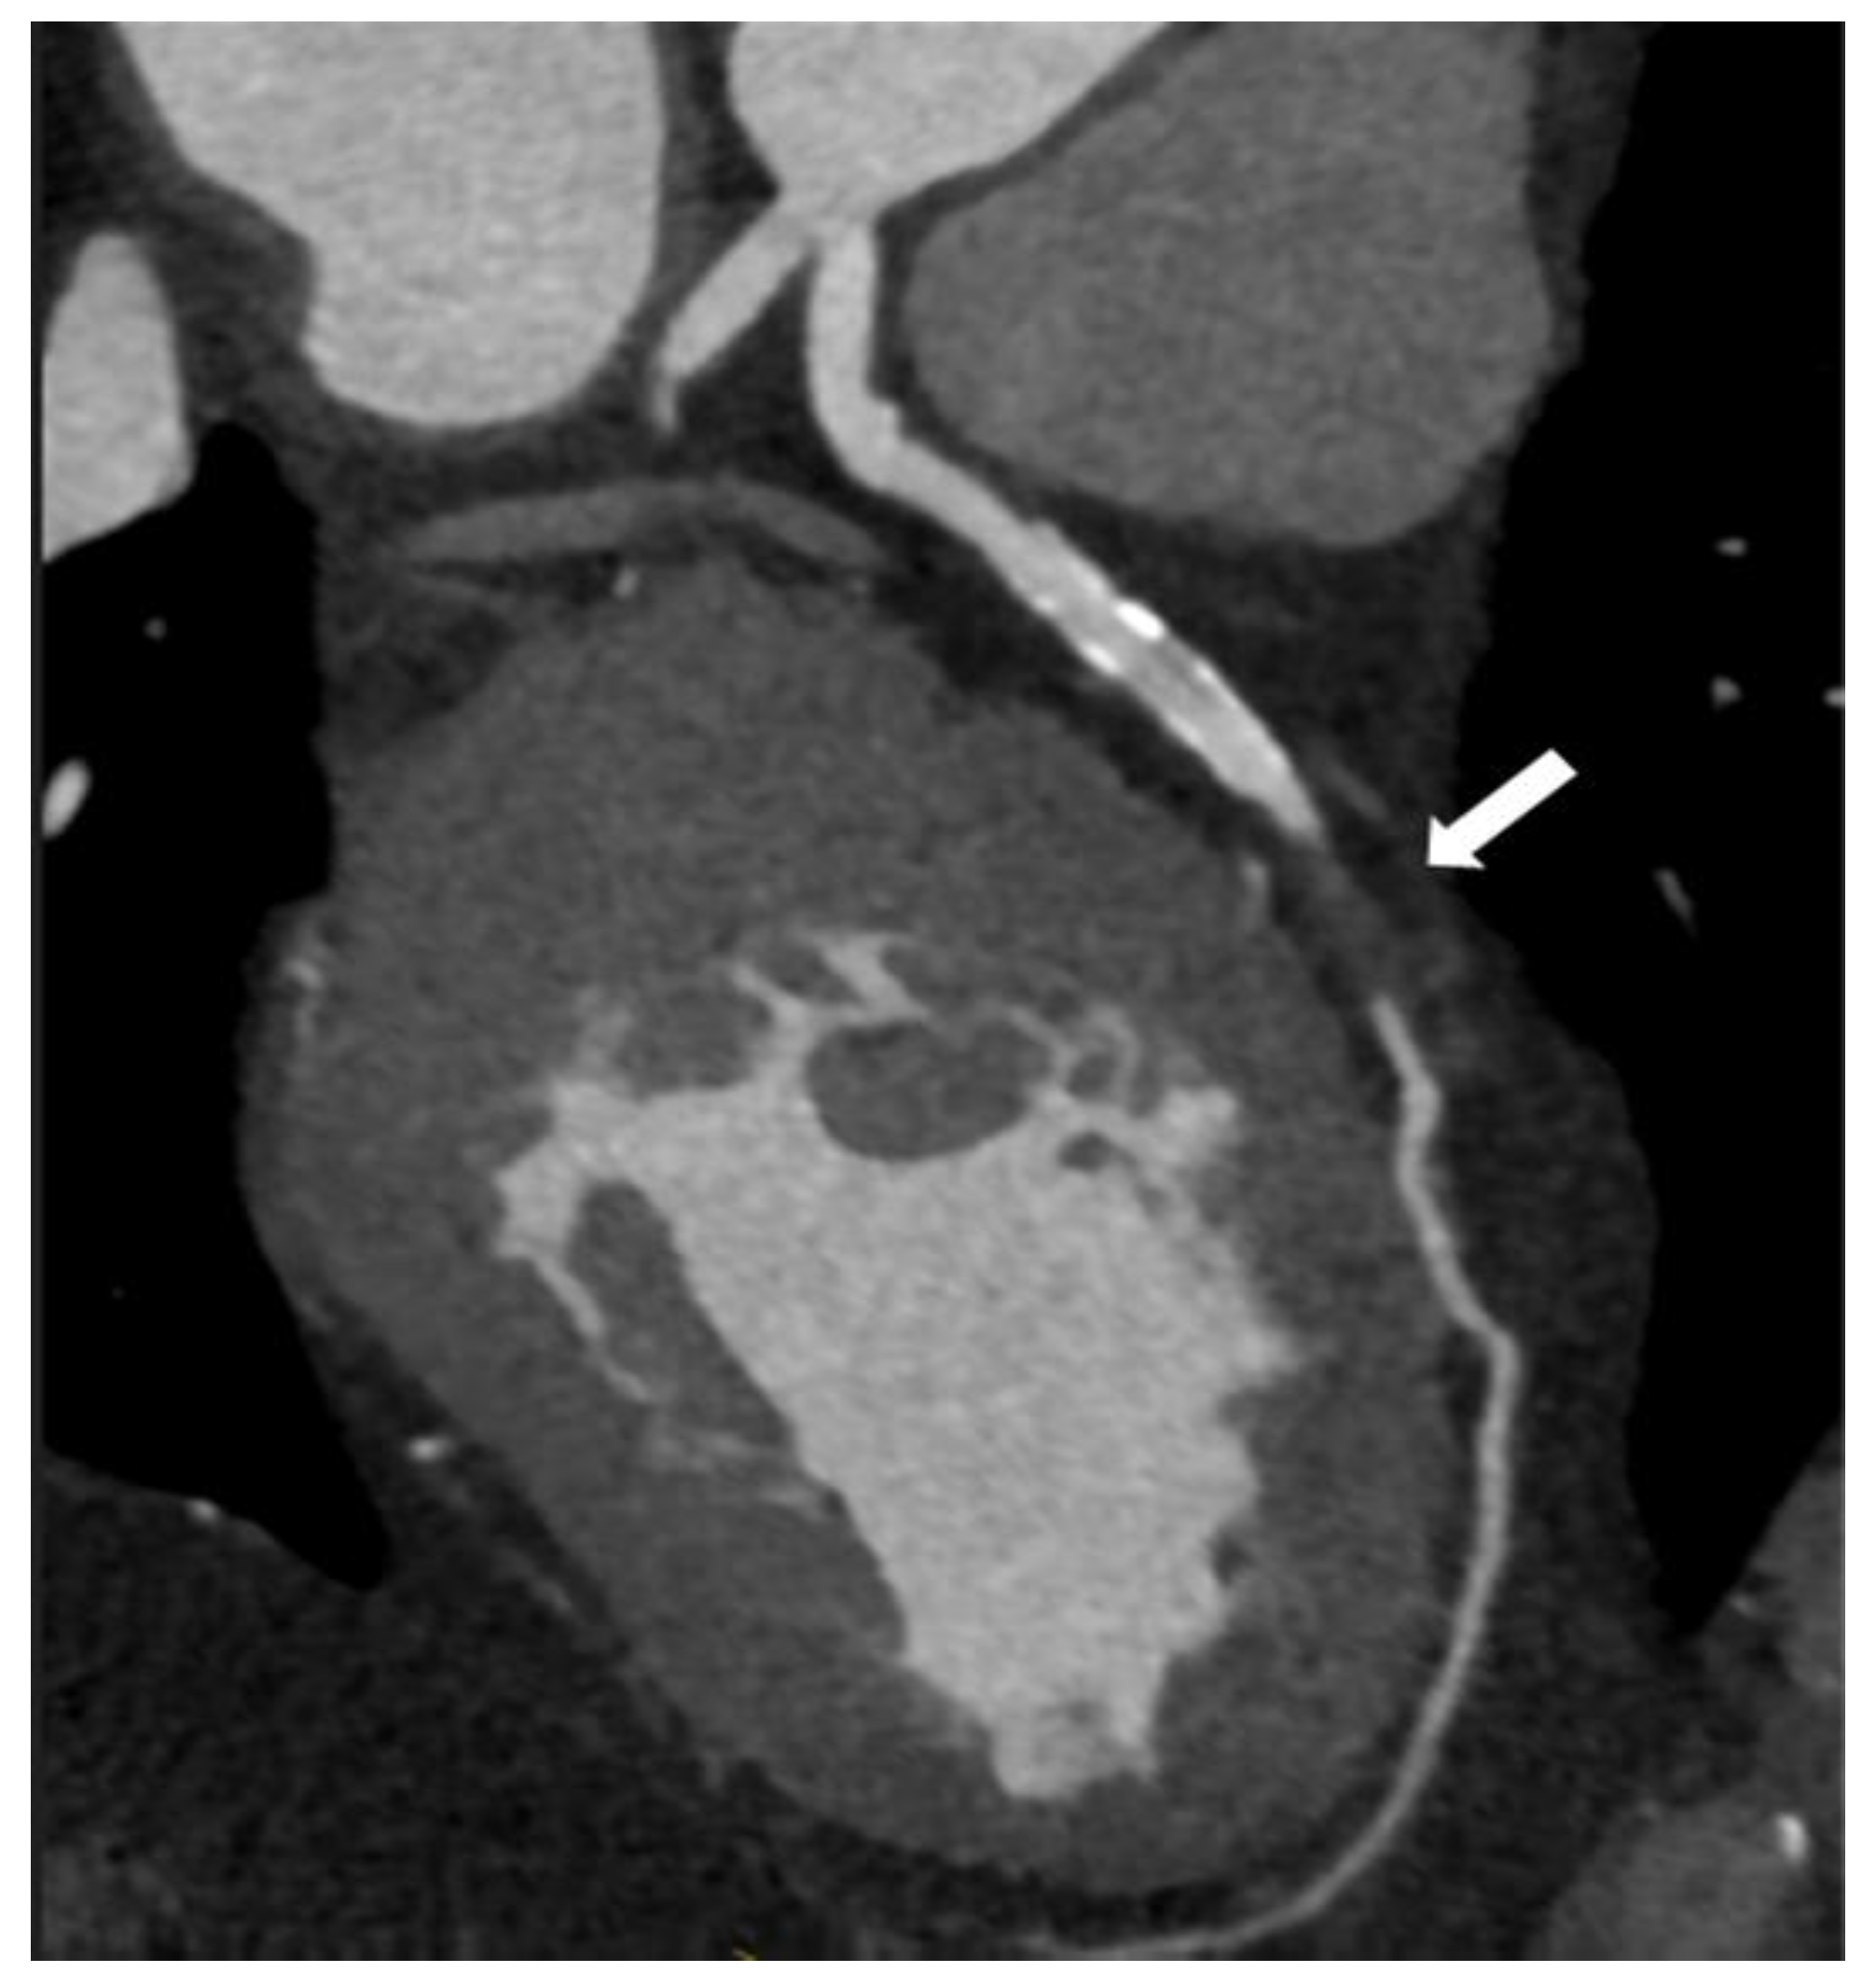

| Coronary computed tomographic angiography (CCTA) | Assess the dimensions and configuration of the arterial wall and lumen Plaque characterization Evaluating the presence, location, and characteristics of aneurysm and stenotic regions Reconstruction of intricate anatomical structures in a three-dimensional model | Noninvasive Greater specificity in cases of aneurysms and thrombosis Suitable for follow-up | Expensive Involves ionizing radiation Requires intravenous contrast media Dependent on an imaging specialist |